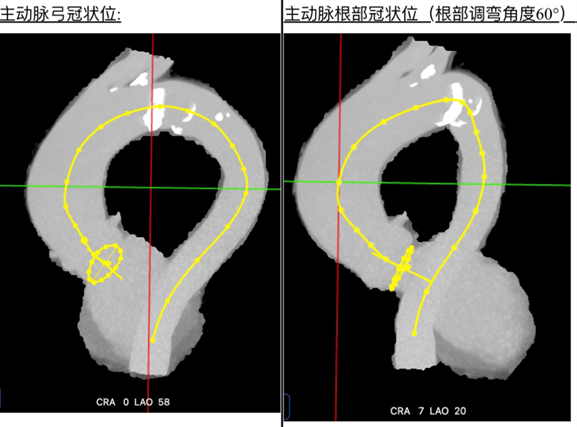

术前CT评估示:升主动脉增宽,主动脉瓣呈三叶瓣,瓣叶增厚,回声增强,瓣叶开放尚可。

二、手术关键步骤:

猪尾导管进窦